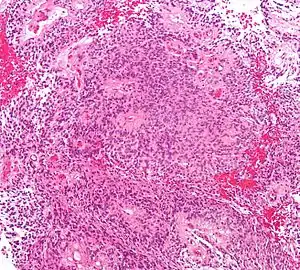

| Micrograph of an ependymoma. H&E stain. | |

Morphology

Ependymomas are composed of cells with regular, round to oval nuclei. There is a variably dense fibrillary background. Tumor cells may form gland-like round or elongated structures that resemble the embryologic ependymal canal, with long, delicate processes extending into the lumen; more frequently present are perivascular pseudorosettes in which tumor cells are arranged around vessels with an intervening zone consisting of thin ependymal processes directed toward the wall of the vessel.[4]